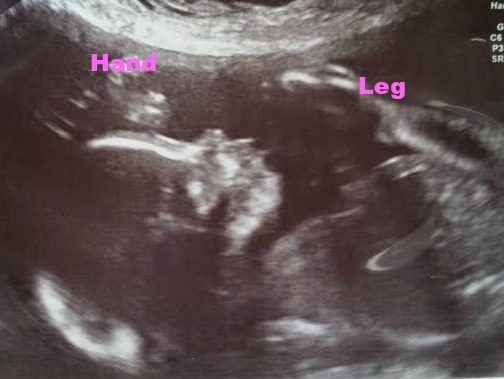

Baby H at my 18w U/S yesterday... After over an hour of looking and measuring and not being able to see the sex due to LO keeping the legs crossed, I was told to empty my bladder and we would try again. LO not only uncrossed it's legs, but completely flipped over... It's a Girl!